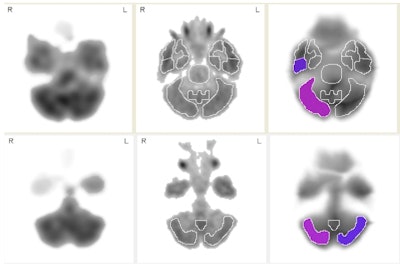

In the comparison of retired players to normal subjects, Raji and colleagues found significantly diminished regional cerebral blood flow in the right inferior lateral posterior temporal cortex and right cerebellum, and significantly elevated regional cerebral blood flow in the right posterior medial temporal cortex and right sensorimotor cortex. Defensive backs had lower blood flow compared to offensive linemen in the left superior frontal cortex.

SPECT images show axial slices from a group of 45 retired NFL players compared to 25 normal controls. Purple and violet regions show increasingly abnormal areas of low blood flow (violet represents a larger deficit in blood flow than purple) in the cerebellum and right medial temporal cortex. The medial temporal cortex is frequently implicated in the pathology of Alzheimer's disease. Image courtesy of Dr. Cyrus Raji, PhD.The most striking finding was the abnormally low areas of blood flow in the right posterior temporal lobe of the retired football players compared to normal subjects, Raji said.

"The temporal lobe finding is especially important because that's the area that often shows early abnormality in dementias, such as frontal temporal dementia or Alzheimer's," he explained. "That is relevant to this study because, even though none of our players had these dementias, traumatic brain injury is a risk factor for dementia."